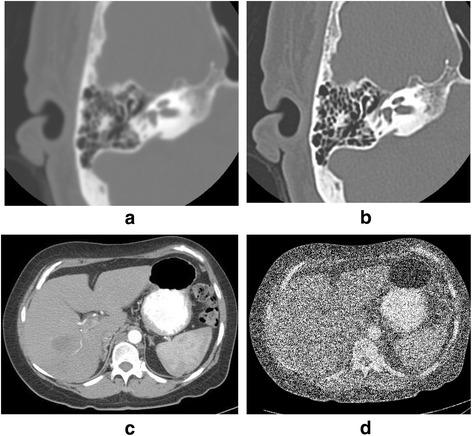

After segmentation or separation of the critical structures, the data are converted into STL files, the standard file format for 3D printing. The STL mesh files, made up of triangles of various shapes and sizes, are processed to varying degrees in order to be accepted by the 3D printing computer. The computer reconstructs or “slices” the STLs files into thin horizontal layers and prints them. There are many processes for fixing or optimizing the mesh for printing including optimizing the shape and number of triangles and decreasing inverted triangles and bad edges. The software also includes methods to fill holes, connect, smooth and expand the mesh surfaces. These processes are used to “clean up” the mesh to allow for printing and to improve the appearance to more closely reflect the source data. However, these processes have limitations and can inadvertently change the appearance of the model, for examples, removing fine structures from the original model and over smoothing and wrapping surfaces so they no longer reflect the source data (Figs. 4 and 5).

Fig. 4.

Infant skull wrapping with different parameters. Excessive wrapping shows loss of detail in the cranial sutures (black arrow) including normal variant accessory parietal suture, and loss of detail and inaccurate representation of anatomic size in the nose, zygoma, cranial vault, and mandible (red asterisk)

Fig. 5.

A trachea model without (a) and with (b) wrapping process. The wrapping process removes distal branches of the trachea (arrows)